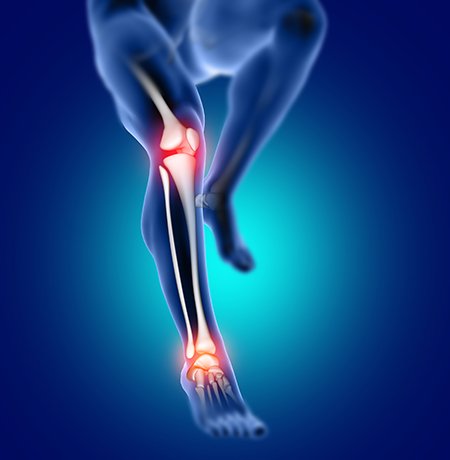

Orthopedics is the medical specialty that focuses on the diagnosis, treatment, and prevention of conditions and injuries affecting the musculoskeletal system, including bones, joints, muscles, ligaments, and tendons.

– Orthopedic specialists address a wide range of musculoskeletal conditions, such as fractures, arthritis, sports injuries, spinal disorders, and deformities.

– Osteoarthritis is a degenerative joint disease that commonly affects weight-bearing joints. Orthopedic specialists provide comprehensive management strategies to alleviate pain and improve joint function.

– Orthopedic specialists play a crucial role in the management of sports-related injuries, including ligament tears, tendonitis, and stress fractures.